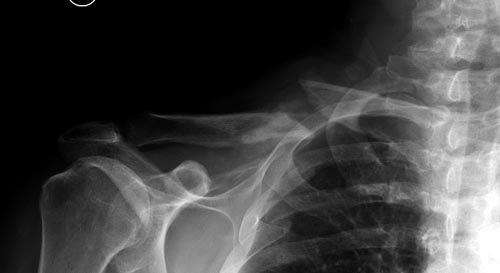

В заключение, только 25% изолированных переломов ключицы, леченных консервативным методом не срастаются, а из них 1/3 симптоматические. Болезненные ложные суставы надо оперировать, и здесь представлен случай свежего болезненного ложного сустава, оперированного через 4 месяца.

Освобожден средний фрагмент и боковая компрессия лагированием, фиксация пластиной..